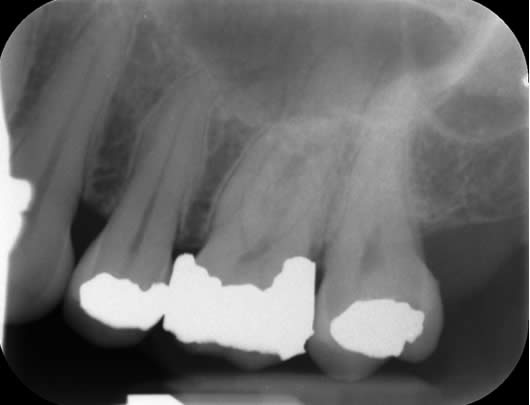

Case 7: Root canal retreatment – a good healing outcome.

In this case, the patient presented with a ‘blister’ in the gum next to her lower right first molar (LL6). The LL6 had a crown and was tender when tapped. There was a small swelling in the gum with a communication, which we call a sinus. We placed a tracer cone within the ‘blister’ and took a radiograph to see where the infection was draining from. This showed that the tooth had a root filling in the canals and a large shadow around one of the roots. The tracer cone was pointing to this large shadow indicating that this was the source of the ‘blister’. It was clear that the previous root canal treatment had failed and it was thought that the reason for the failure was persistent infection or reinfection of the canals. After discussion of treatment options, we decided to do root canal retreatment. The previous root canal filling was removed from all canals. The canals were then shaped, cleaned and filled again. In between the two treatment visits, the ‘blister’ had healed. We reviewed the tooth one year later and the patient reported that the tooth had been fine. We took a radiograph and could see that the ‘shadow’ had gone and the lesion had filled with new bone.

Before our treatment- the canals contain the root filling from the previous treatment. The tracer cone is pointing to the large ‘shadow’.

After completion of root canal retreatment

1 year review showing complete healing of the previous ‘shadow’.